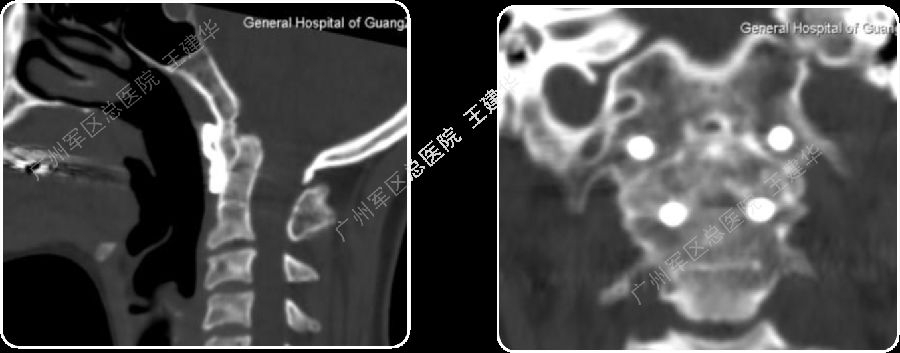

手术后CT显示,陷入枕骨大孔的齿突获得下拉复位

手术后2年复查的CT,显示侧块关节已经完全融合

颅颈椎序列恢复正常并骨性融合